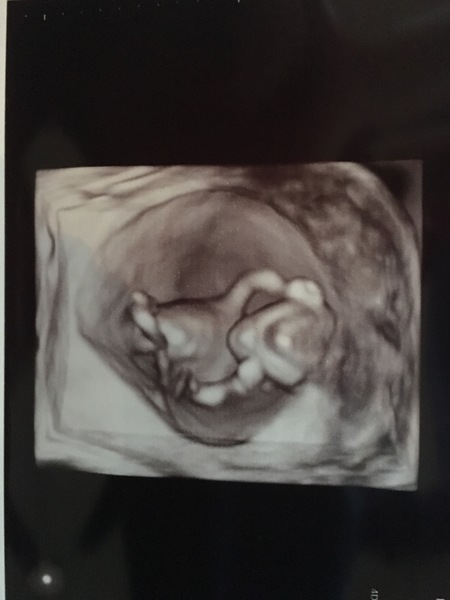

We had our scan on Thursday and oh my god isn't it the most magical thing seeing that little heartbeat?! He/she was bigger than expected putting me at 13 weeks so my due date has changed to the 4th Dec!

Congrats @BeeMama2017 ! Great pic!

Congrats bee that's a fabulous picture! I hope wedding planning is going well and you have a brilliant day next week xx

Lovely scan pic BeeMama 😀

Aww @BeeMama2017 that's a lovely pic! Congrats and good luck for the last week of wedding prep 🎉

Bee congratulations, what a lovely scan pic ❤️

Congratulations BeeMama, lovely scan! Good luck for next weekend, hope all your final planning goes smoothly 🙂

Lilly I had a private NT and other scan as part of my harmony test, it was much more detailed than the NHS equivalent and I'm glad we had both. Even got the freaky 3D pic attached which I wasn't expecting!! Would very much recommend the fetal medicine centre if you're around London.

Congrats @Lixon 😀 cool pic